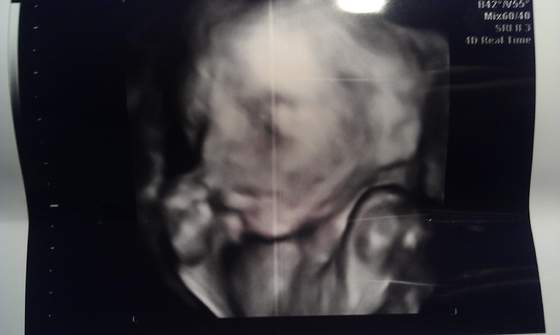

oregano gratulacje - dawaj mi fluidy dziewczęce!!!! i koniecznie wklej zdjęcia!!!